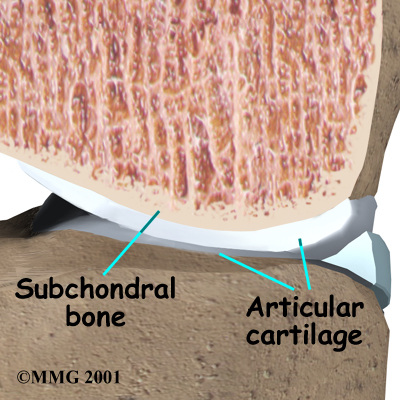

The main problem in OA is degeneration of the articular cartilage. Articular cartilage is the smooth lining that covers the ends of the leg bones where they meet to form the knee joint. The cartilage gives the joint freedom of movement by decreasing friction. The layer of bone just below the articular cartilage is called subchondral bone.

Scientists believe that problems in the subchondral bone may trigger changes in the articular cartilage. Normally, the articular cartilage protects the subchondral bone. But some medical conditions can make the subchondral bone too hard or too soft, changing how the cartilage normally cushions and absorbs shock in the joint.